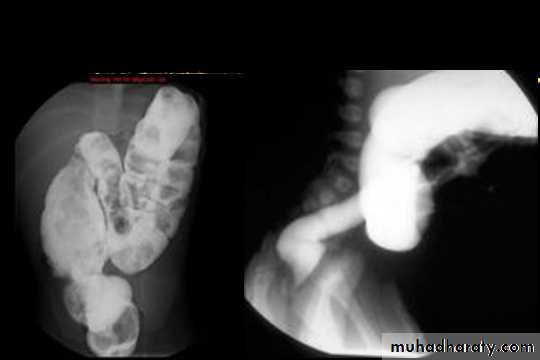

Crohns Disease :

• Crohn disease remains idiopathic• Radiographic features

• The characteristic of Crohns disease is the

• presence of :

• _skip lesions

• _multiple discrete ulcers.

Radiological finding of CD in BA follow through :

• _Multiple mucosal ulcers aphthous ulcers.• _Transmural ulcer (Rose thorn appearance )

• _longitudinal fissures

• _Multiple skip lesions

• _when severe leads to cobblestone appearance

• _May lead to sinus tracts and fistulae

• _widely separated loops of bowel due to fibro-fatty proliferation

• _Thickened folds due to edema.

• _Pseudo diverticula formation: due to contraction at the site of ulcer with ballooning of the opposite site.